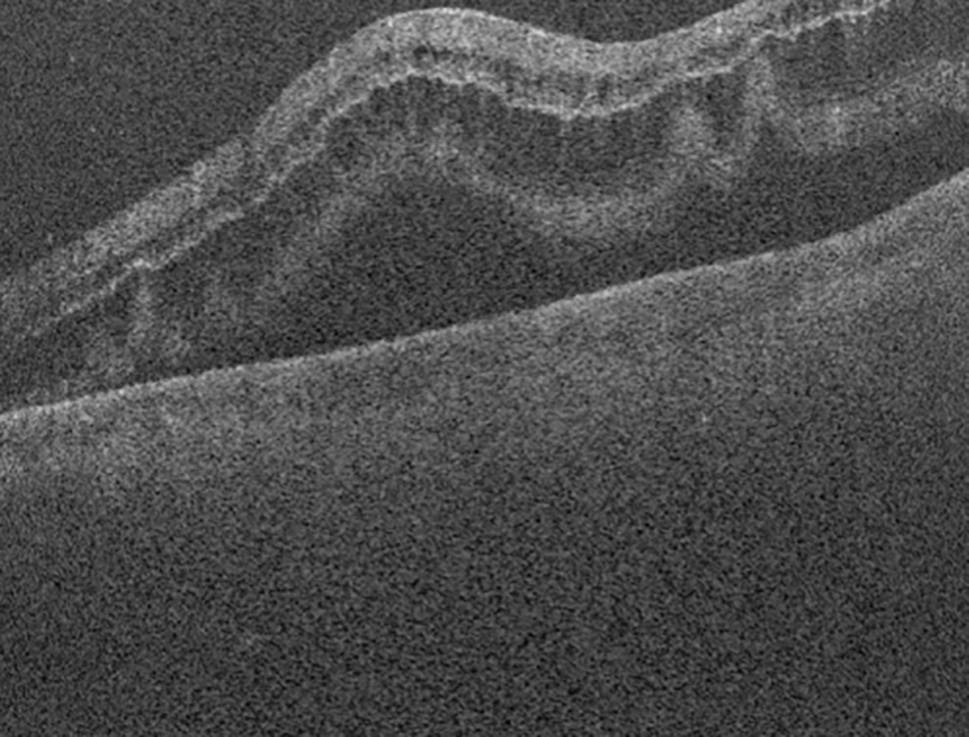

Fig. 12

Optical coherence tomography image demonstrating reattachment of the macula after vitrectomy surgery

Optical coherence tomography (OCT) is a noninvasive test that utilises light reflected to provide a cross-sectional image of the retinal layers [71]. It can assist in the detection of microstructural changes that are not always clinically evident, such as the presence of subretinal fluid at the macula in an RRD (“macula-on” or “macula-off”). These classifications have important implications for surgical timing and the visual prognosis. Macula-on RRDs typically have better VA on presentation and yield better visual prognoses. Surgery is typically performed within 24 h. Macula-off RRDs present with worse visual acuities and tend to have worse visual prognoses despite successful retinal reattachment [6].

Postoperatively, OCTs can also indicate important anatomic abnormalities after retinal reattachments, such as cystoid macula oedema, disruption of the ellipsoid zone/external limiting membrane, epiretinal membrane, disruption of retinal layers, retinal folds, outer retinal corrugations and residual subfoveal fluid [72]. These are important in explaining and predicting visual prognoses and metamorphopsia despite successful reattachment [71]. More recently, OCT angiography (OCT-A) has helped to predict visual prognosis after macula-off retinal detachment repairs, particularly due to the detection of an enlarged foveal avascular zone (FAZ) and reduced vessel density in the choriocapillaris [73].